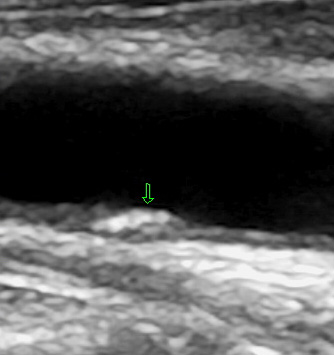

Auf den Bildern sehen Sie einerseits eine glatte Halsschlagader, die Sie schon als solche

erkennen können, weiter eine Halsschlagader mit beginnender Ablagerung (Plaques) und

eine Halsschlagader mit deutlichen Plaquebildungen bis insgesamt zu einer mindestens

70 %igen Verengung. Das erkennt man an dem schwarzen noch offenen Lumen.